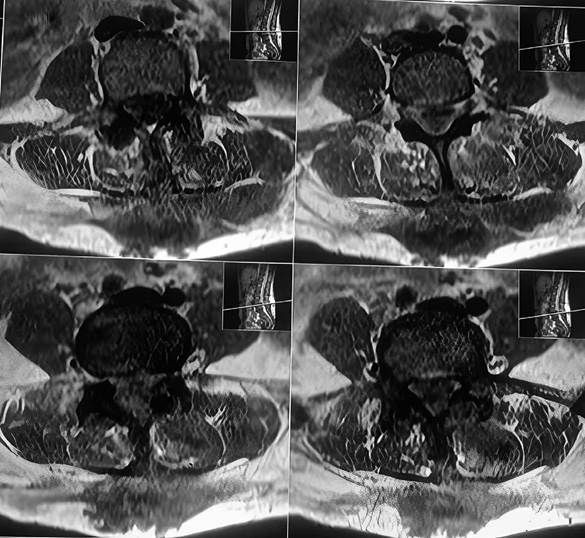

Al cuadro se suma alzas térmicas hasta 38,5 ° que ceden con paracetamol de forma parcial, taquicardia persistente y clínicamente presencia de fluctuación del nódulo proveniente de la línea media de la espalda por lo que se desde realizar una resonancia magnética de columna lumbosacra en la cual se observa colección en planos superficiales posteriores (paraespinosos), y otras colección que se dirige hacia canal medular a nivel de L4-L5, además de protrusión discal L4-L5 subarticular derecha sin compromiso radicular y protrusión discal subarticular derecha de L5-S1 con compromiso radicular ipsilateral, hiperdensidad de apofisis espinosas de L3-L4.

Fig 3. RMN cortes axiales de columna lumbosacra potenciada en T1 muestra colección mal definida, de contornos irregulares, heterogénea, de predominio hipointensa, localizada en plano de tejido celular subcutáneo que contacta con plano muscular y apófisis espinosa de L2, L3, y L4

En resonancia magnética, los cambios son visibles de forma precoz a 3 o 5 días desde el inicio de la infección, con una sensibilidad del 96% y especificidad del 93%. Por esto mismo, las guías IDSA 2015 recomiendan el estudio con resonancia magnética en todos los pacientes con sospecha de infección espinal. Los cambios característicos en resonancia magnética dependen de la secuencia que se esté analizando. En secuencia T1, se encontrará hipo intensidad de señal del cuerpo y plataforma vertebral, así como del disco intervertebral comprometido y borramiento del límite cuerpo-disco. En secuencia T2, veremos hiperintensidad de señal del cuerpo y plataforma vertebral, así como del disco intervertebral comprometido y pérdida de la hendidura intranuclear característica. Finalmente, en la secuencia con gadolinio, destacará el refuerzo periférico en anillo de las lesiones del cuerpo, plataforma y disco.8